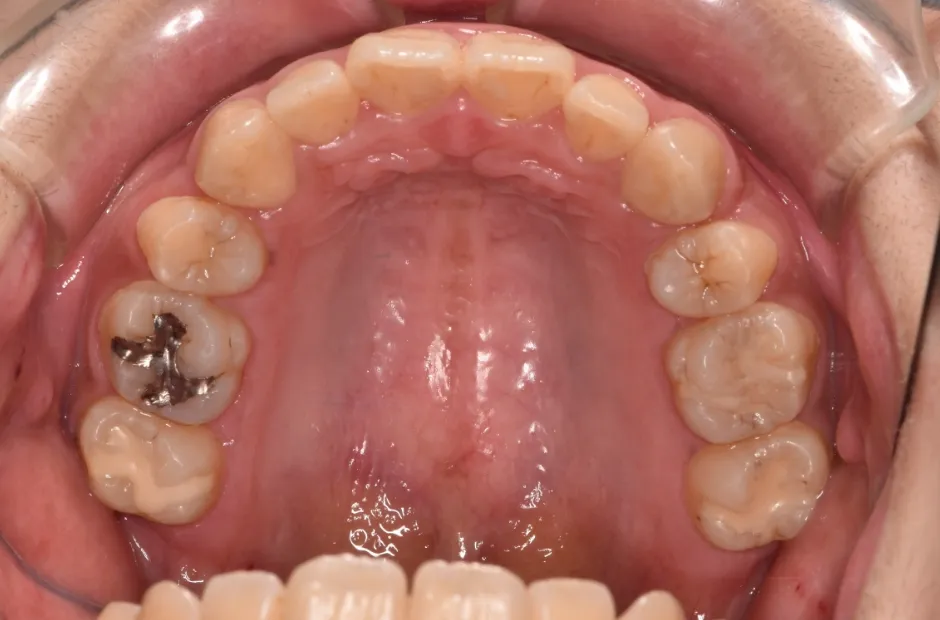

| 診断名・主訴 | 開咬 |

|---|---|

| 年齢・性別 | 23歳・女性 |

| 治療期間・回数 | 1年 12回 |

| 治療に用いた主な装置 | クワドヘリックス(QH)+タングガード → ロール付きリンガルアーチ |

| 抜歯部位 | 左右下8番 |

| 治療費 | 70万円(税抜) |

| リスク・副作用 | 装置による違和感・疼痛・歯肉退縮・歯根吸収・虫歯のリスクなど |

治療前